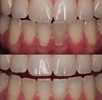

Kanal Tedavisi

Mikroskop ile Kanal Tedavisi

Mikroendodonti